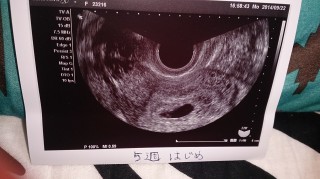

• おなまえあかね

• ねんれい24

• 妊娠週5w3d

6w5dだったけど大きさで5w3dになりました! 心拍がピコピコ動いてて可愛かったあ(^ω^)